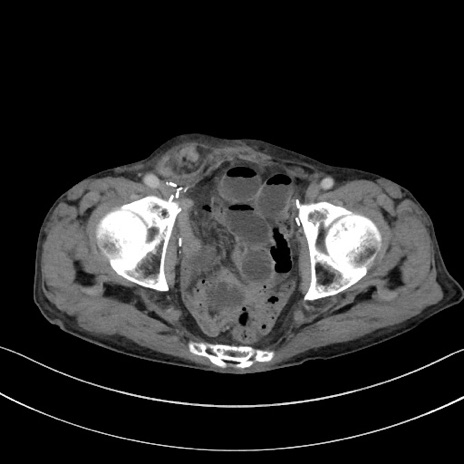

矢状断像

【症例】 70歳代男性

【主訴】右鼠径部腫瘤、疼痛

【現病歴】本日朝より上記主訴あり、受診。

【既往歴】膀胱癌にて膀胱全摘、両側尿管皮膚瘻

【データ】WBC 5600、CRP 0.56